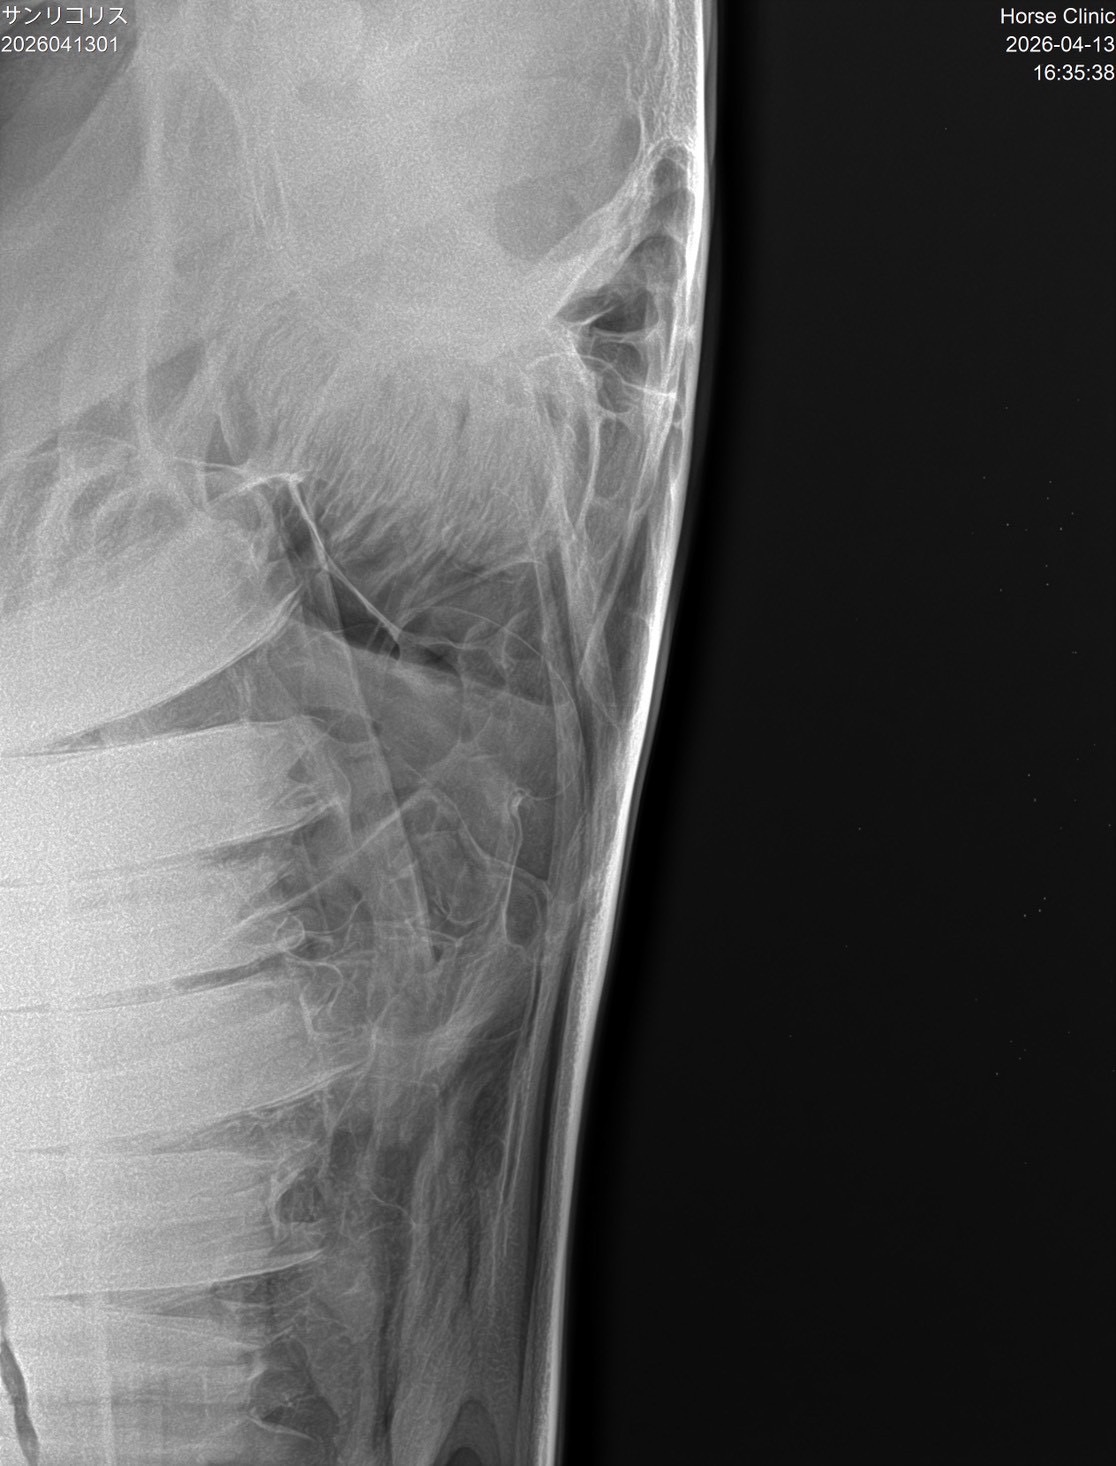

【本馬についての現状説明】

転厩当初から鼻水が止まらない状態で使っています。蓄膿症の症状で、治療は続けていますが、良くならないので、競馬でも影響が出ていると思います。頭数整理でオークション出品となりました。(川崎競馬・山崎裕也調教師)